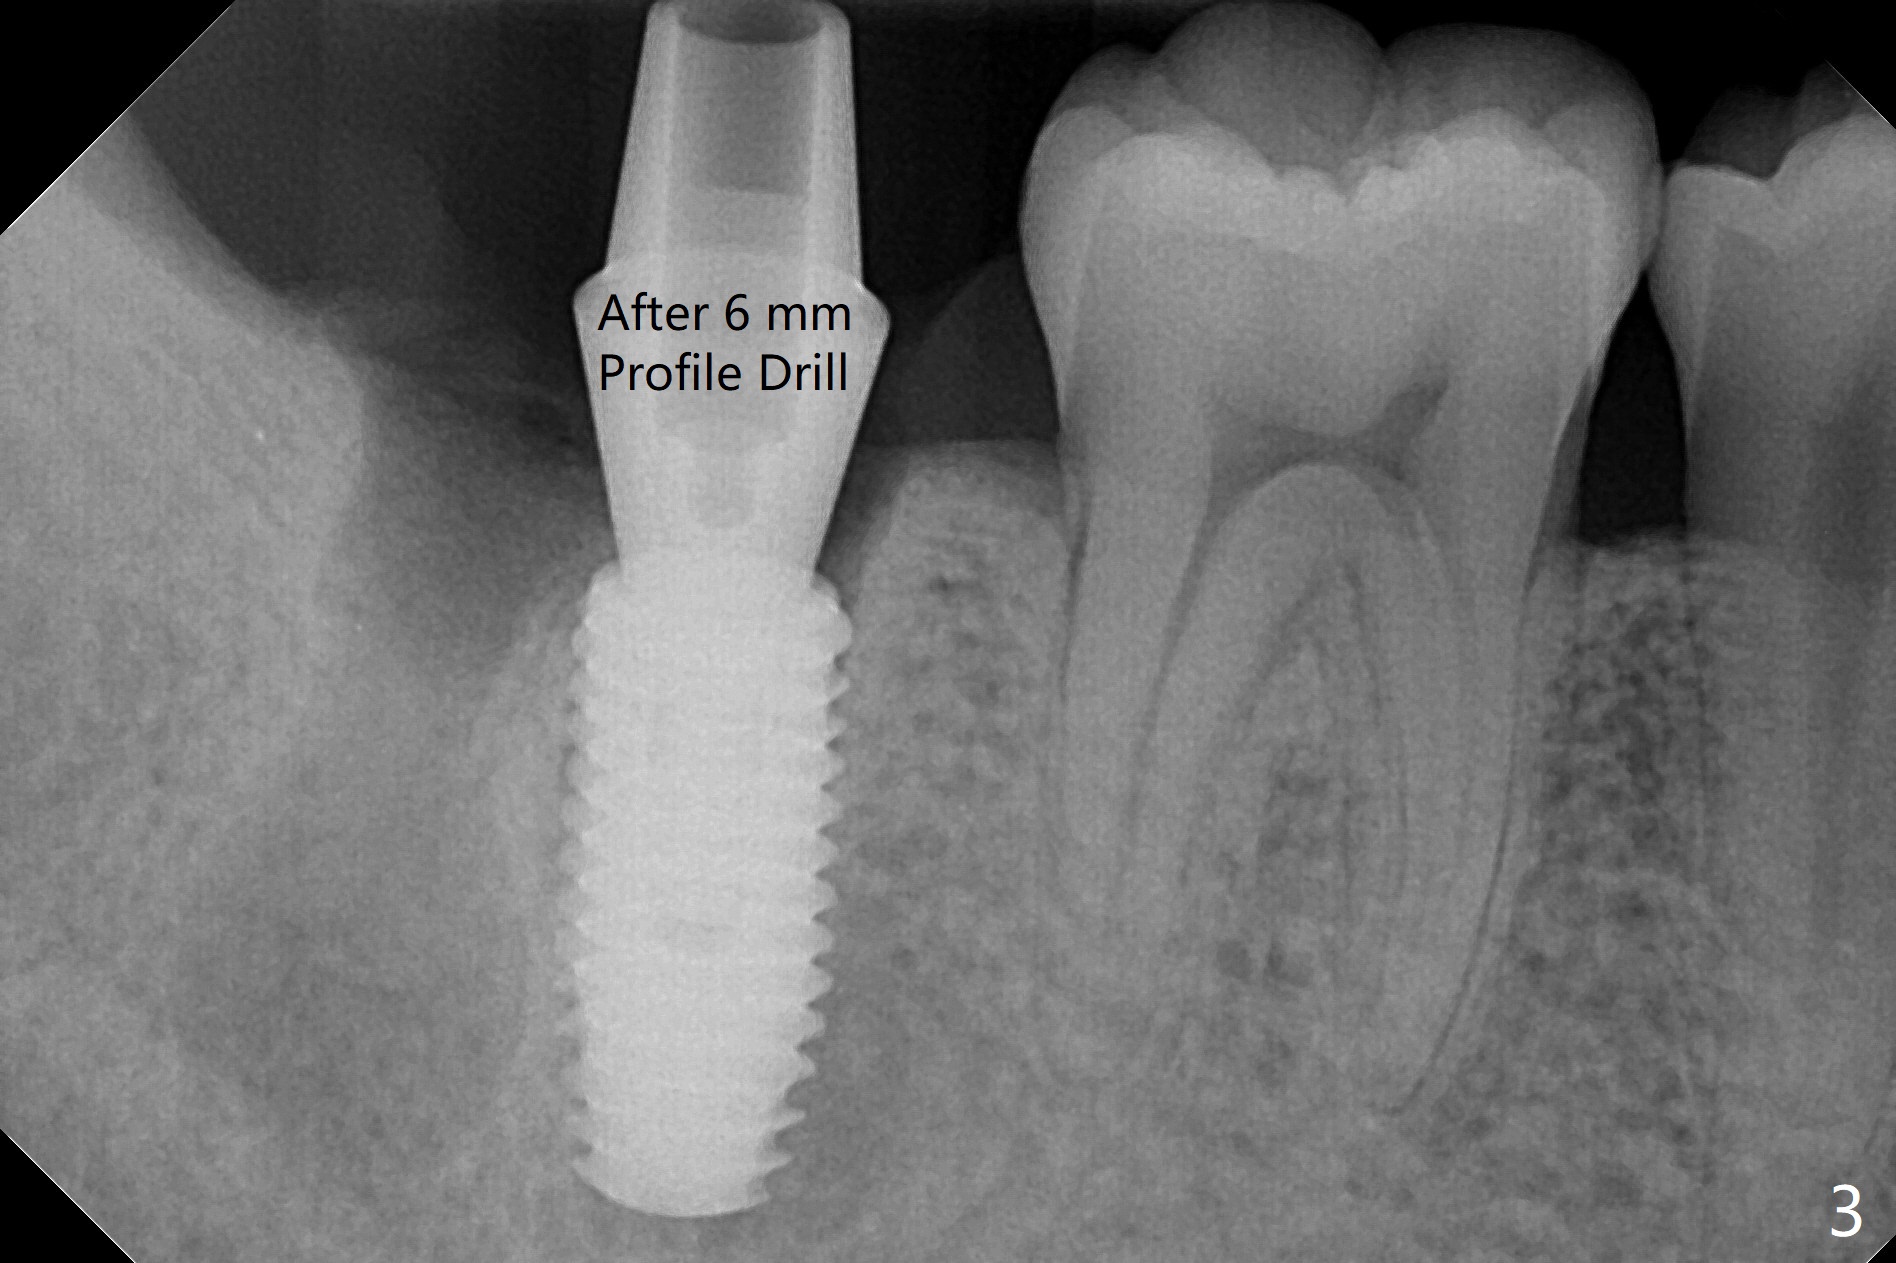

考虑到31号牙严重骨质吸收尤其是远中窝根尖(图一:*),实验室建议钻洞直径要比植体小三号(3.5毫米钻头;5.0毫米植体),其实行不通,使用4.0毫米钻头后,勉强植入4.5毫米报废植体(图一),阴差阳错:植体进入近中牙槽窝,植体四周都有骨壁包绕,包括远中:中隔(S)。最后为了使用5x11.5毫米植体,必须用4.5毫米钻头和5毫米皮质骨攻螺纹(到第三格,多3毫米,图二);放置基台好像没有就位。使用6毫米profile drill(好像去除舌侧中隔)后,手感基台就位,但是根尖片显示(图三)与图二没有区别(植体太粗,看不清楚植体与基台接触)。放置粘性骨粉后(图四),制作临时牙冠,放置PRF后,衬里多次增加固定和与牙龈密合度。术后医嘱包括手术区不使用水牙线。术后一周复诊询问骨粉游出问题。如果第二下磨牙种植能够进入近中窝,不必使用导板,4.5毫米足够,X光片观察基台就位也容易。术后三个月骨粉好像转变成正常骨质(图五,六, 30 Ncm)。